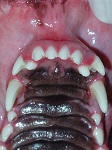

An owner requests that you perform orthodontics on his show dog, since the maxillary incisors have gaps bilaterally, and this causes the dog to loose points in the ring.  You evaluate the mouth and see the following:

Hyperdontia Supernumerary Tooth Dec 2008-01

a) There is a slight gingivitis present on the incisor and canine teeth of the maxilla (as the rest of the teeth are out of focus they are not evaluated in this photograph).

Furthermore, there are 2 increased distemas between the 2nd and 3rd incisors of both the maxillae.

Eight incisors are present instead of 6, with both the extra (supernumerary) incisors positioned palatally and rotated.